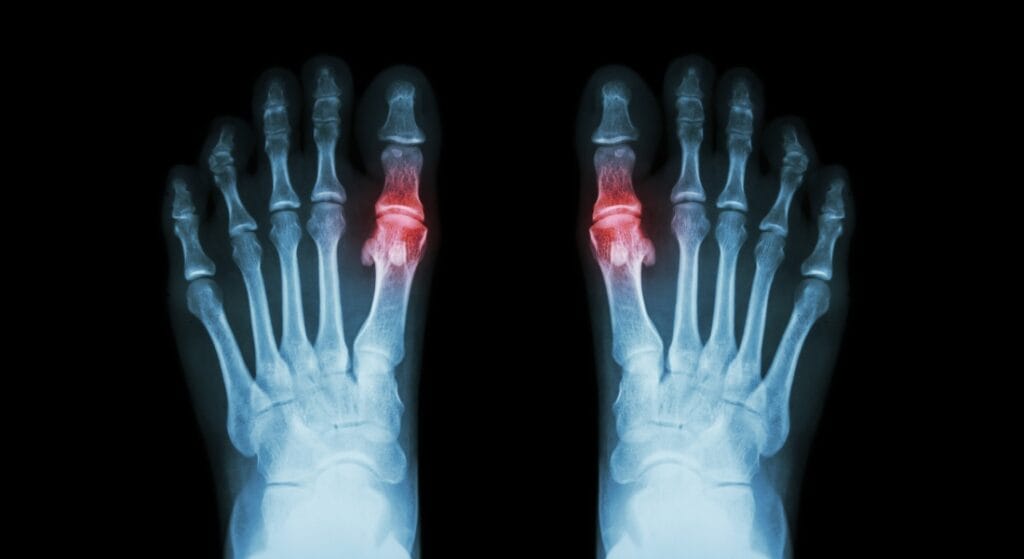

- Biến dạng khớp, mất chức năng vận động: Các khớp bị viêm kéo dài sẽ dần biến dạng, lệch trục, teo cơ, mất khả năng cử động bình thường.

- Teo cơ, dính khớp: Viêm lâu ngày làm các cơ quanh khớp yếu dần, khớp có thể dính cứng, khiến người bệnh mất khả năng tự đi lại, phụ thuộc vào người khác.